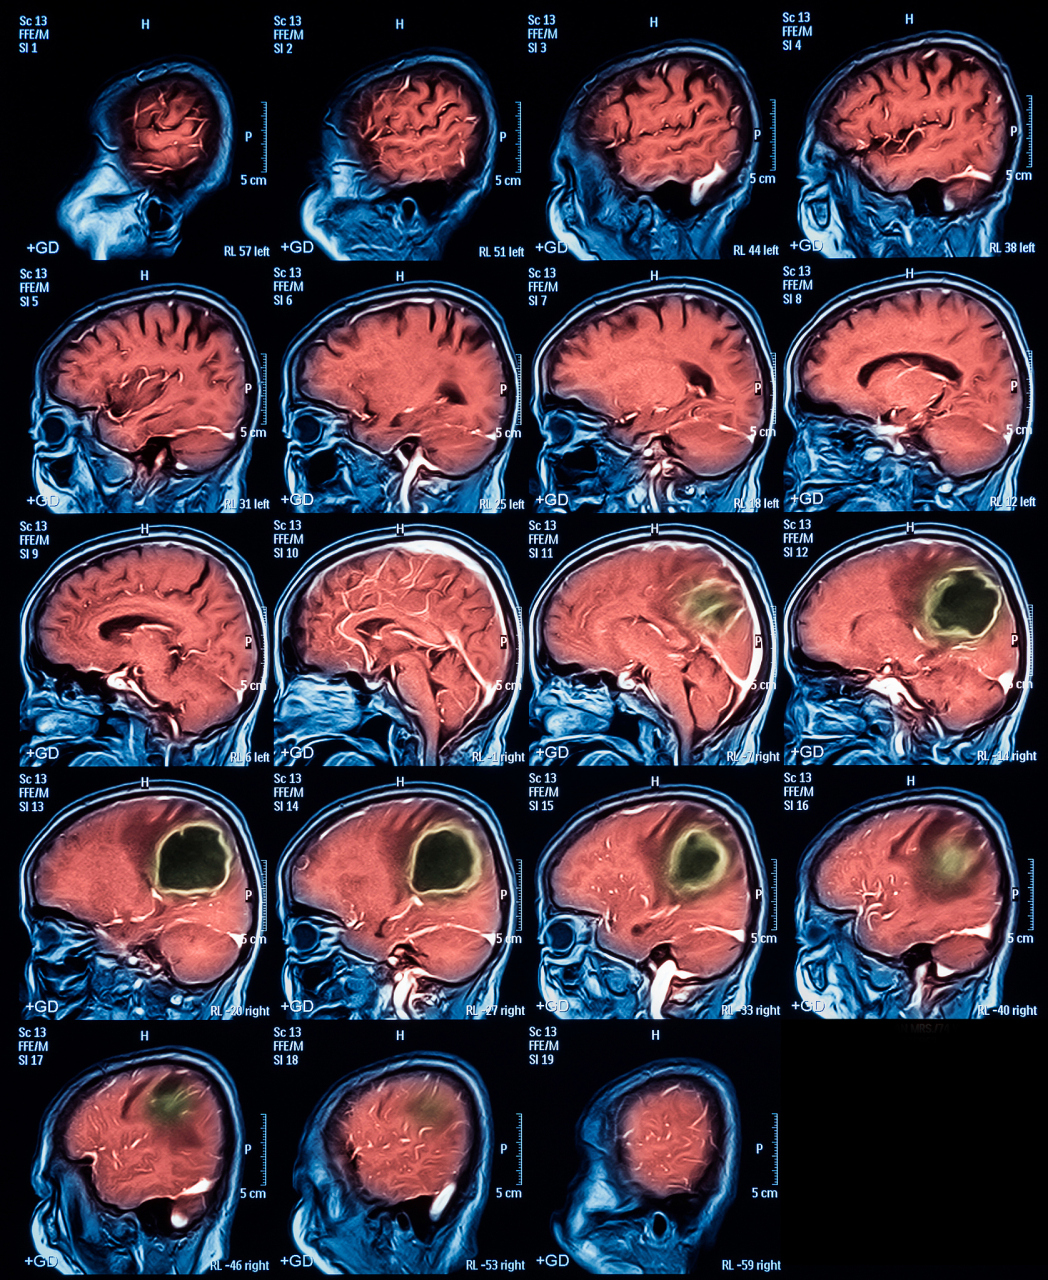

95亚急性脑梗死mri影像学习